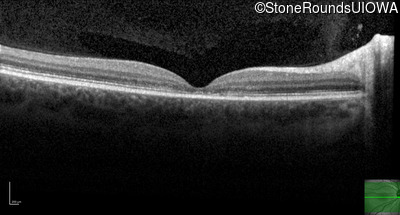

AR Stargardt Disease (IIA)

Age at visit: 20 years

Age at visit: 22 years

This 20 year old man first noticed some difficulty reading the board at school in 9th grade 20 in 2017